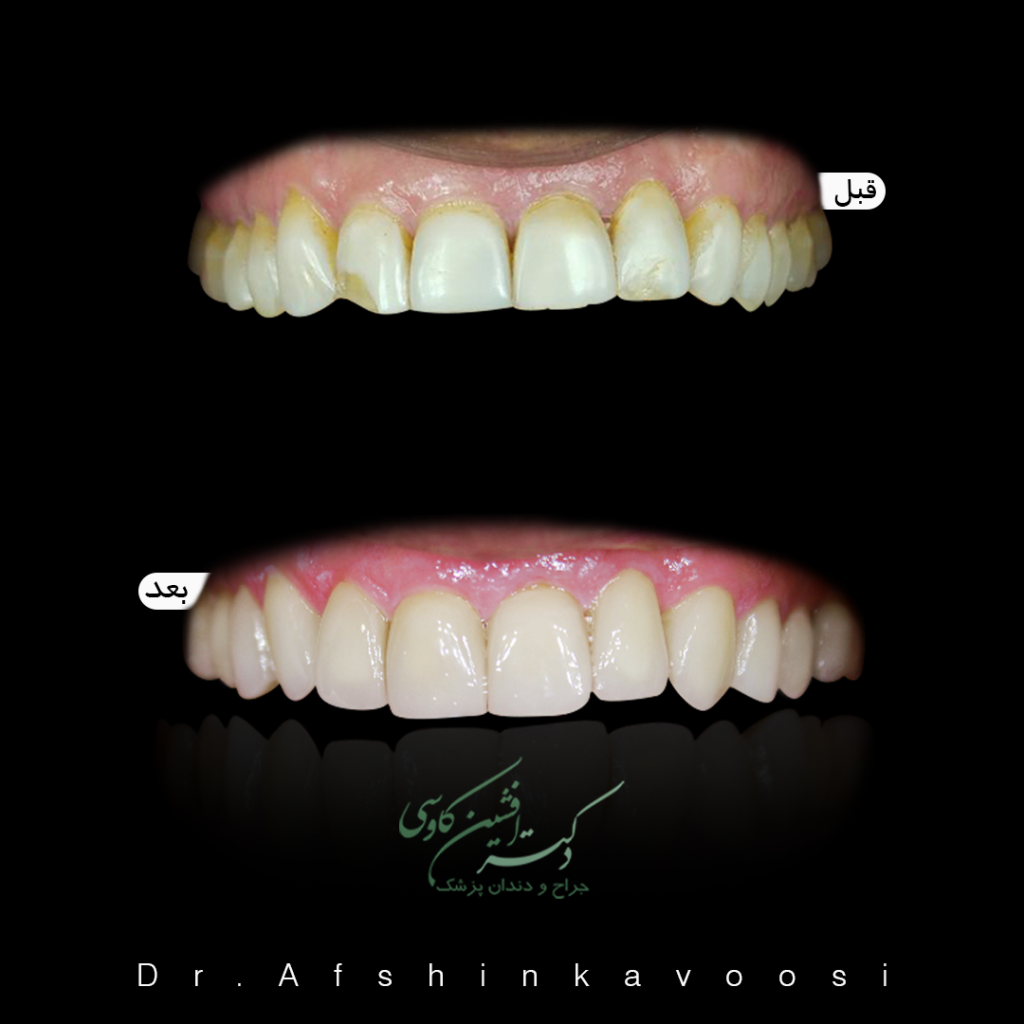

لامینت های سرامیکی

در گالری های زیر نمونه ای از درمانهای ونیر سرامیکی یا همان لامینت را مشاهده می فرمایید